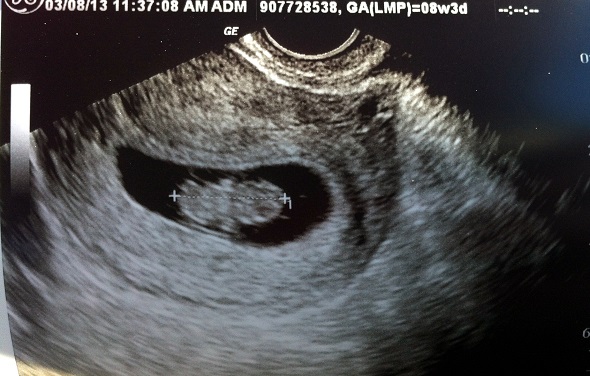

Baby Size: Raspberry. It definitely doubled in size because I had to have a 2nd ultrasound the week after the first because I was still having some spotting from my appointment. Everything was okay – it was just a precaution. You can see little arm and leg buds!

Best moment of the week: Another tie. I already mentioned the 2nd ultrasound – which was a total bonus – and it was great to see that the baby had doubled in size in a week. I felt a lot more confident after that. The other best moment(s) were telling my family. We went to visit my family since we hadn’t been home since Christmas and we had a free weekend. I bought a “big sister” dog shirt for Boof to wear and that’s how we decided we’d tell my family since they love when she visits.

Milestones: 2nd ultrasound